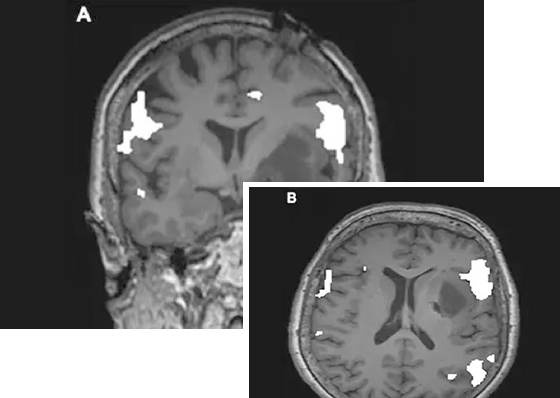

(越来越多的文献报道验证了LITT治疗癫痫的有效性,图片来自INC之加拿大James Rutka教授的学术沙龙PPT)